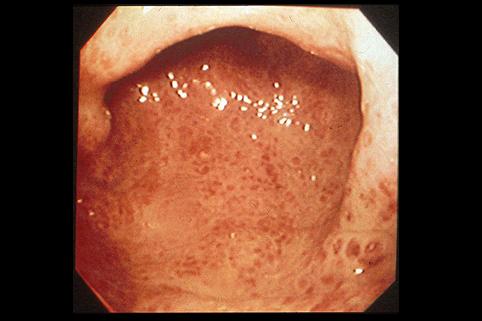

질환(병리주체)의 분류 악성 상피성종양/선암

부위(장기별) 대장/2구역 이상의 대장에 걸치는 것

검사방법 내시경

종양의 육안분류 4형(미만침윤형)/

종양의 최대경(밀리미터) 40이상

종양의 심달도 ss(a1)